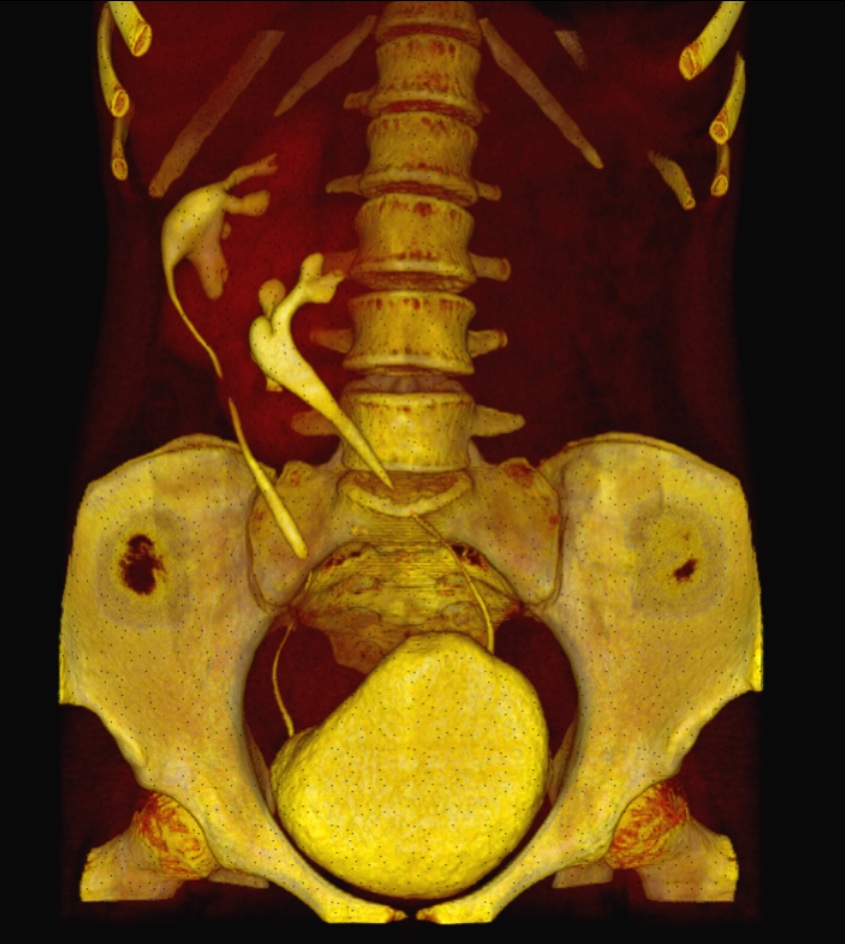

Caso #1: Ectopía Renal Cruzada Fusionada

Paciente femenina en la que se identificó ausencia de riñón izquierdo en fosa renal, con fusión renal en flanco derecho. Las reconstrucciones 3D y cortes axiales confirman una ectopía renal cruzada tipo A con malrotación de ambos riñones. Cada uréter conserva su trayecto anatómico hacia su meato correspondiente en vejiga.

Corte axial TC Reconstrucción 3D 1 Reconstrucción 3D 2 Plano sagital VR uréteres